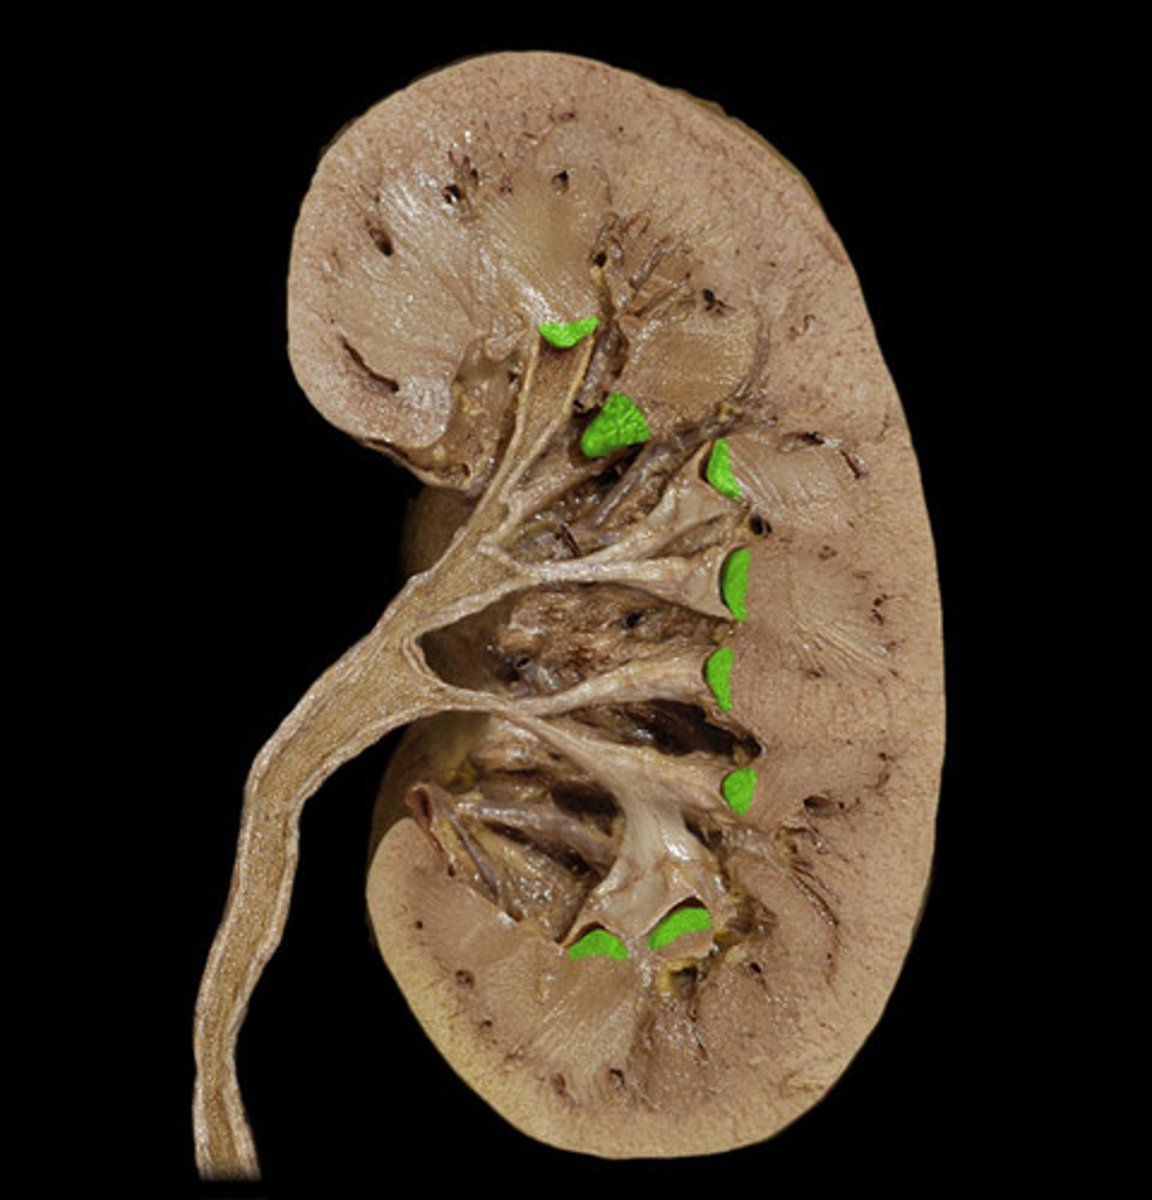

What is this?

Minor calyx

Major calyx